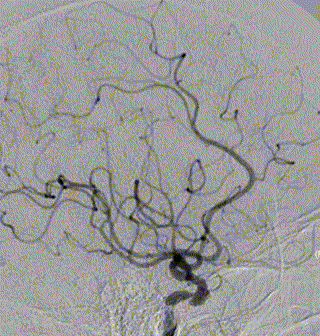

脑血管造影提示右侧颈内动脉颅内段多发动脉瘤(反主动脉弓)

脑血管造影提示右侧颈内动脉颅内段多发动脉瘤